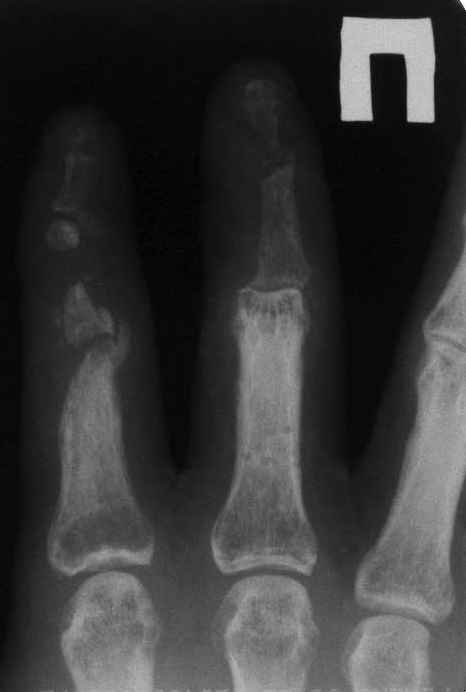

На представленных снимках пальцы правой кисти мужчины 42 года через 3 месяца после травмы циркулярной пилой.

Качательные движения в проксимальном м/ф суставе 3 пальца. Нарушены все виды захвата, в которых принимают участие 2 и 3 пальцы. Кожные покровы с большими рубцами по тыльной и боковой поверхности пальцев. Ни магистральный кровоток, ни микроциркуляция специальными методами не оценивались. Косвенно о трофических нарушениях свидетельствует распространенный остеопороз дистальных фаланг и очаговый остеопороз основных фаланг и головок пястных костей, причиной которого возможно является и длительная иммобилизация в аппарате внешней фиксации. Чувствительных нарушений нет.

Планируем: 3 палец - открытый артродез дистального м/ф сустава с минимальной фиксацией спицей, тенолиз и разработка проксимального сустава (по этому пальцу в общем тактика ясна). 2 палец - обсуждается два варианта тактики:

1. Остеотомия основной фаланги, с последующей дистракцией в аппарате и удлинением последней до дистального м/ф сустава. Далее снова остеотомия - или неартроз, или эндопротез проксимального сустава, тенолиз. (Недостаток - будет потеряно время для восстановления функции сухожилий)

2. Костная пластика средней фаланги, одновременно тенолиз, артродез дистального м/ф сустава, разработка захватов. (Недостаток - опасаемся возможного некроза трансплантата вследствие ангиотрофических нарушений)Буду признателен за высказанные на форуме мнения по поводу пациента.